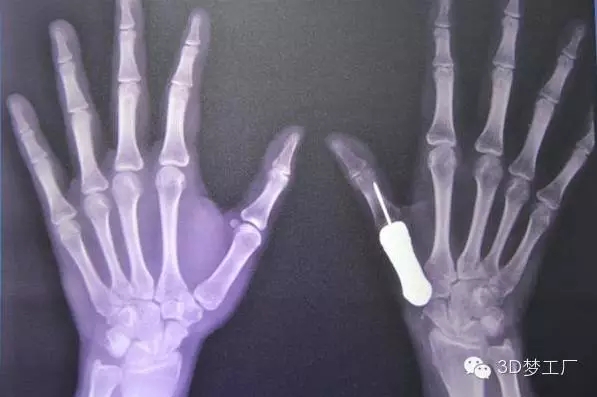

2016年1月26日,泰國(guó)曼谷Phramongkutklao醫(yī)院的醫(yī)生們宣布,他們成功用3D打印鈦金屬假體替換了一個(gè)拇指掌骨。這在世界上還是第一次。該醫(yī)院骨科主任Thipachart Punyaratabandhu博士在宣布這則消息的同時(shí)詳細(xì)介紹了他的團(tuán)隊(duì)是如何將一個(gè)3D打印的鈦金屬拇指指骨植入一位女性患者的手上,這位患者原來的指骨由于腫瘤的出現(xiàn)已經(jīng)惡化。

治療團(tuán)隊(duì)一開始對(duì)病人健康的左手拇指進(jìn)行掃描和拍攝X光片,然后用鏡像的方法渲染出她的右手拇指指骨原來應(yīng)有的樣子,并用樹脂材料3D打印出其模型,最后用一種醫(yī)用鈦金屬鑄造出來。整個(gè)制造過程總共只用了一個(gè)星期左右,但是Phramongkutklao 醫(yī)院骨科的醫(yī)生團(tuán)隊(duì)為了研發(fā)這個(gè)3D打印拇指項(xiàng)目已經(jīng)耗費(fèi)了將近兩年時(shí)間。

據(jù)了解,手術(shù)治療是從去年6月份開始的,當(dāng)時(shí)醫(yī)生將惡化的骨頭從病人手里取出來,并等了一段日子以確保腫瘤不會(huì)復(fù)發(fā)。當(dāng)這一情況在9月下旬確認(rèn)之后,外科醫(yī)生繼續(xù)手術(shù),植入鈦金屬指骨并將其與最近的肌腱連結(jié)在一起。